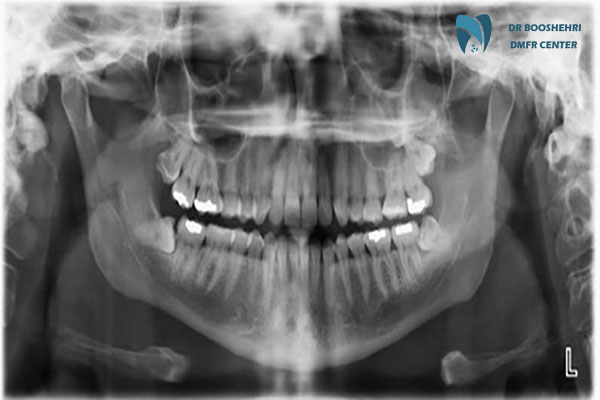

CBCT Dental is one of the most advanced imaging methods, offering high precision in Jaw Disease Diagnosis and gum conditions. Unlike traditional methods such as panoramic radiography, this technology utilizes 3D Dental Imaging, allowing for a detailed view of jaw structures, joints, teeth, and surrounding tissues. This high accuracy enables dentists and specialists to detect issues such as cysts, tumors, bone resorption, and even hidden fractures with greater clarity.

3D Dental Imaging is one of the most effective tools for accurately diagnosing jaw and gum lesions. This advanced technology enables the visualization of jaw and dental structures in three dimensions, making it easier for specialists to detect hidden injuries, infections, and abnormalities. In 2D imaging methods, some crucial details may not be visible, but CBCT Dental, with its high-resolution images, reveals even the smallest changes in jaw and gum tissues.

Compared to traditional methods such as panoramic and periapical radiography, CBCT Dental offers numerous advantages. One of its most significant benefits is providing high-resolution 3D images, allowing for a more detailed examination of jaw and gum structures.

Traditional dental imaging methods often provide 2D images, which cannot accurately depict the depth and precise details of the jawbone and gum diseases. In contrast, 3D Dental Imaging delivers complete information on the condition of teeth, jaw, and surrounding tissues. This advantage is particularly important in Jaw Disease Diagnosis, jaw surgeries, dental implant planning, and orthodontic treatments.